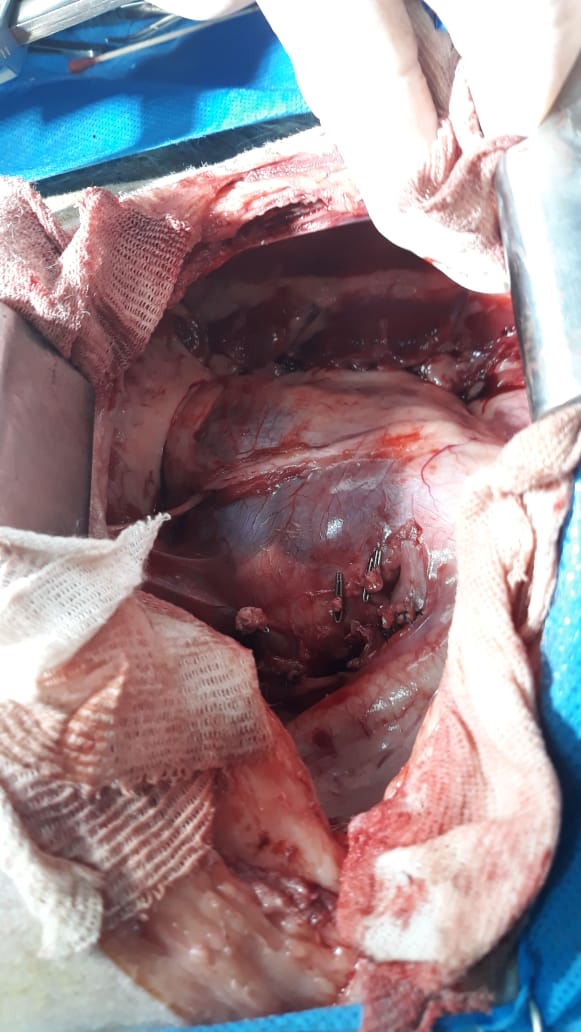

Cirugía

En líneas generales la ablación total del tumor es la terapia más recomendada para los tumores benignos (papilomas, fibromas, leiomiomas). Sin embargo, en los casos de carcinoma urotelial, en donde la diseminación neoplásica y su infiltración local hacen difícil la extracción total del tumor, la cirugía citorreductiva puede constituír una alternativa. En muchos casos puede generar una mejora de la calidad de vida del paciente al lograr una desobstrucción y reinserción de uréteres. El punto es que si bien esto puede ser válido para mejorar el aspecto clínico no constituye una modalidad de terapia que por si sola otorgue mejoras en la sobrevida global de los pacientes.